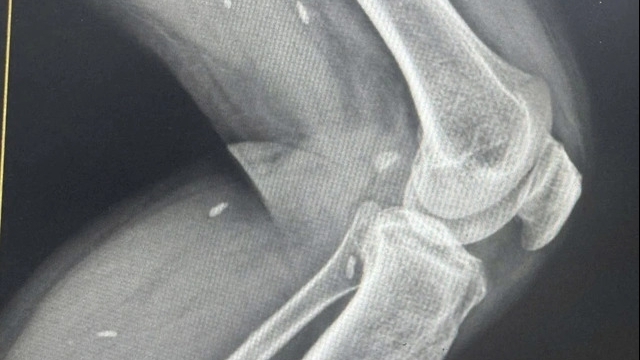

Kết quả thăm khám và xét nghiệm cho thấy cháu bị nhiễm vi khuẩn tụ cầu vàng, đường vào là vị trí bị lợn cắn (tên khoa học: Staphylococcus aureus), kèm tổn thương hai xương đùi, viêm xương đùi phải, áp xe cơ, viêm phổi, tràn dịch màng. Sau 20 ngày điều trị, bệnh nhân có giảm sốt nhưng vẫn đau nhiều khớp háng hai bên, không đi lại được nên tiếp tục chuyển tuyến đến Bệnh viện Bệnh Nhiệt đới Trung ương.

Tại đây, bệnh nhi được chẩn đoán: Nhiễm khuẩn huyết do tụ cầu vàng có viêm xương tủy- áp ce cơ- viêm phổi màng phổi, sau 11 ngày điều trị bằng kháng sinh đặc hiệu và phục hồi chức năng, cháu đã giảm sốt, hết tràn dịch màng phổi và có thể đi lại. Các tổn thương ở xương vẫn cần tiếp tục điều trị và theo dõi dài hơn nhưng hiện nay chưa phải can thiệp ngoại khoa.